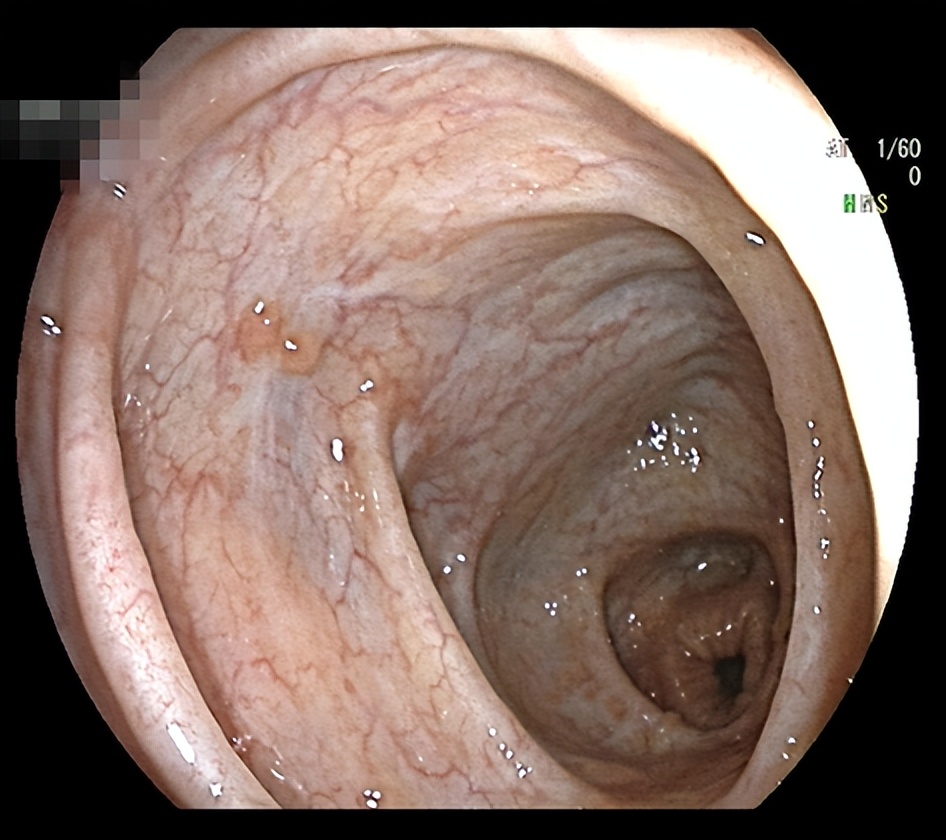

经过新乡医学院第一附属医院炎症性肠病MDT团队讨论,决定为姑娘使用“绿色疗法”,也就是生物制剂。经过治疗后,姑娘的肠子恢复如下: